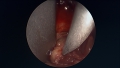

Nous avons décrit une technique endoscopique mini-invasive que nous avons publiée dans l'American Journal of Sports Medicine. Elle s'avère sûre et reproductible dans ses résultats avec un taux plus faible de complications. C'est notre technique de choix de réparation de ces lésions du biceps, notamment chez le sportif de haut niveau comme les rugbymen.